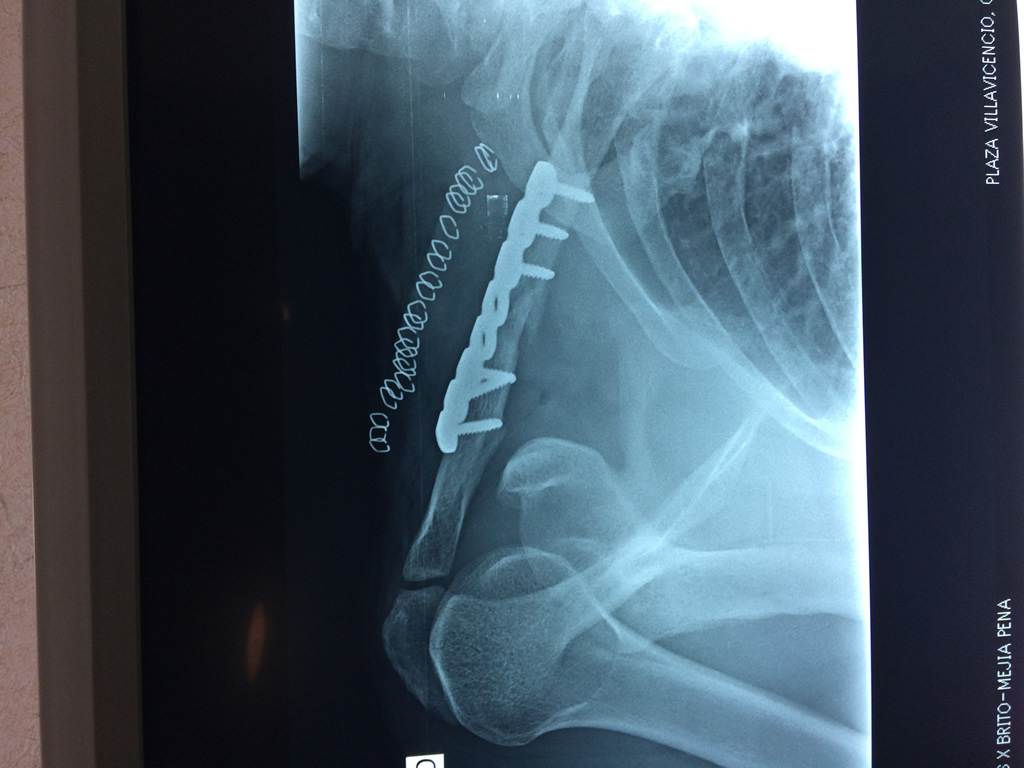

Húmero - Clavícula